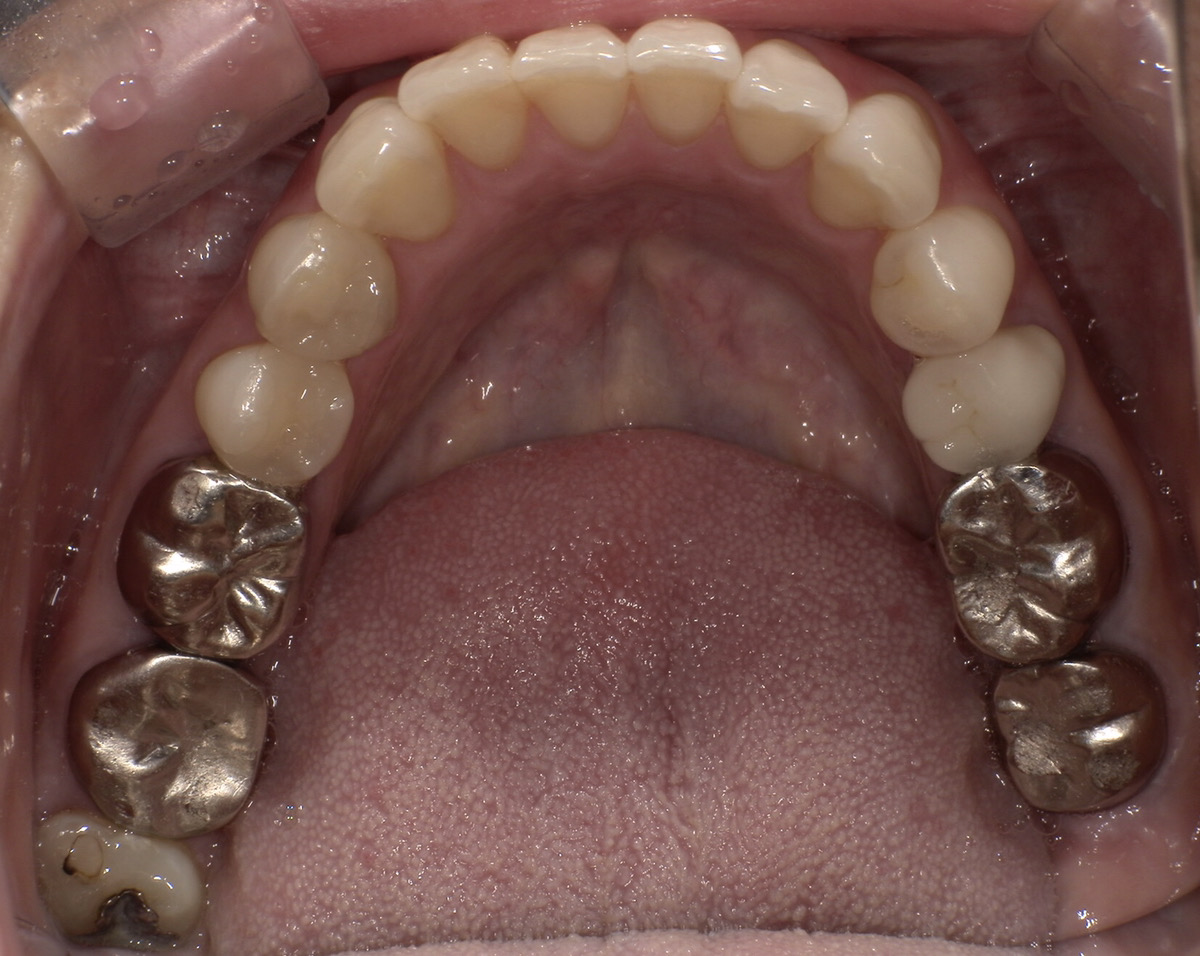

CASE 03

Before

After

施術内容左右下顎の第一・第二大臼歯の銀歯(被せ物)をジルコニアクラウンに交換。右下第二小臼歯の銀歯(詰め物)をジルコニアインレーに交換。

治療期間3か月

リスク・副作用ジルコニアは非常に強度が高いですが、強い衝撃や極端に強い噛み合わせ、歯ぎしり・食いしばりなどがある場合、まれに割れたり欠けたりする可能性があります。

費用 454,400円

※表示金額は全て税込みです。